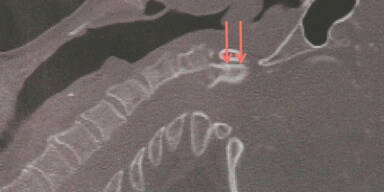

Die Steirerin wurde mit dem Hubschrauber ins LKH Graz geflogen und dort noch am gleichen Tag operiert. In der zweistündigen OP schoben die Ärzte den gebrochenen Halswirbel wieder an die richtige Stelle und fixierten ihn mit einer vier Zentimeter langen Schraube. Bereits am darauffolgenden Tag begann die 64-Jährige mit ihren "Therapie-Tauchgängen" in einer Druckkammer.